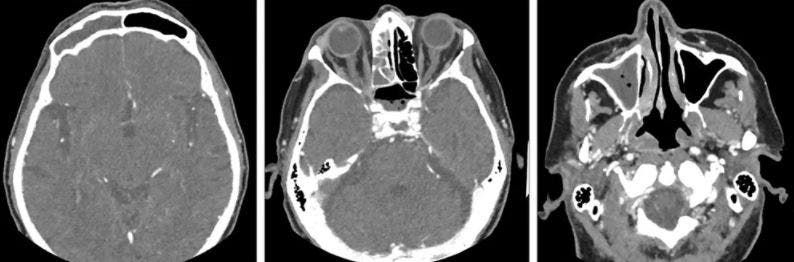

إلى ذلك، كشف التصوير المقطعي أن مصدر معاناة المريض هو التهاب الجيوب الأنفية الذي يمتد إلى الجانب الأيمن من وجهه.

وكانت الحالة خطيرة للغاية، حيث تسببت في تآكل العظم نفسه، ما استلزم إجراءً طارئاً لإزالة أكبر قدر ممكن من المادة الملتهبة من كل تجويف.

صور مقطعية للدماغ (آيستوك)